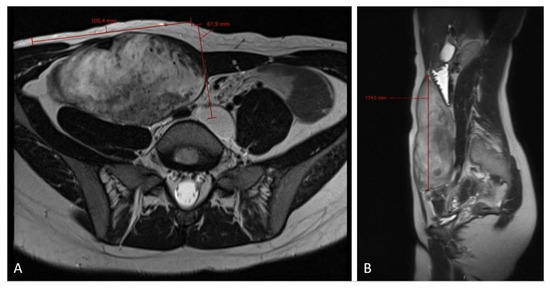

Figure 5.

MRI scan ((A)—axial plane; (B)—sagittal plane) after 3 cycles of chemotherapy showing no effect of the treatment and slight progression in the craniocaudal tumor size (12.0 × 6.6 × 20.0 cm).